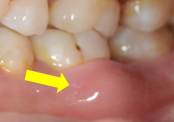

牙龈肿痛溢脓                            牙齿松动、移位、脱落